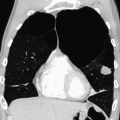

A chest X-ray and complete blood count may be useful to exclude other conditions at the time of diagnosis.[61] Characteristic signs on X-ray are overexpanded lungs, a flattened diaphragm, increased retrosternal airspace, and bullae while it can help exclude other lung diseases, such as pneumonia, pulmonary edema or a pneumothorax.[62] A high-resolution computed tomography scan of the chest may show the distribution of emphysema throughout the lungs and can also be useful to exclude other lung diseases.[15] Unless surgery is planned, however, this rarely affects management.[15] An analysis of arterial blood is used to determine the need for oxygen; this is recommended in those with an FEV1 less than 35% predicted, those with a peripheral oxygen saturation of less than 92% and those with symptoms of congestive heart failure.[14] In areas of the world where alpha-1 antitrypsin deficiency is common, people with COPD (particularly those below the age of 45 and with emphysema affecting the lower parts of the lungs) should be considered for testing.[14]

Very severe emphysema with lung cancer on the left (CT scan)